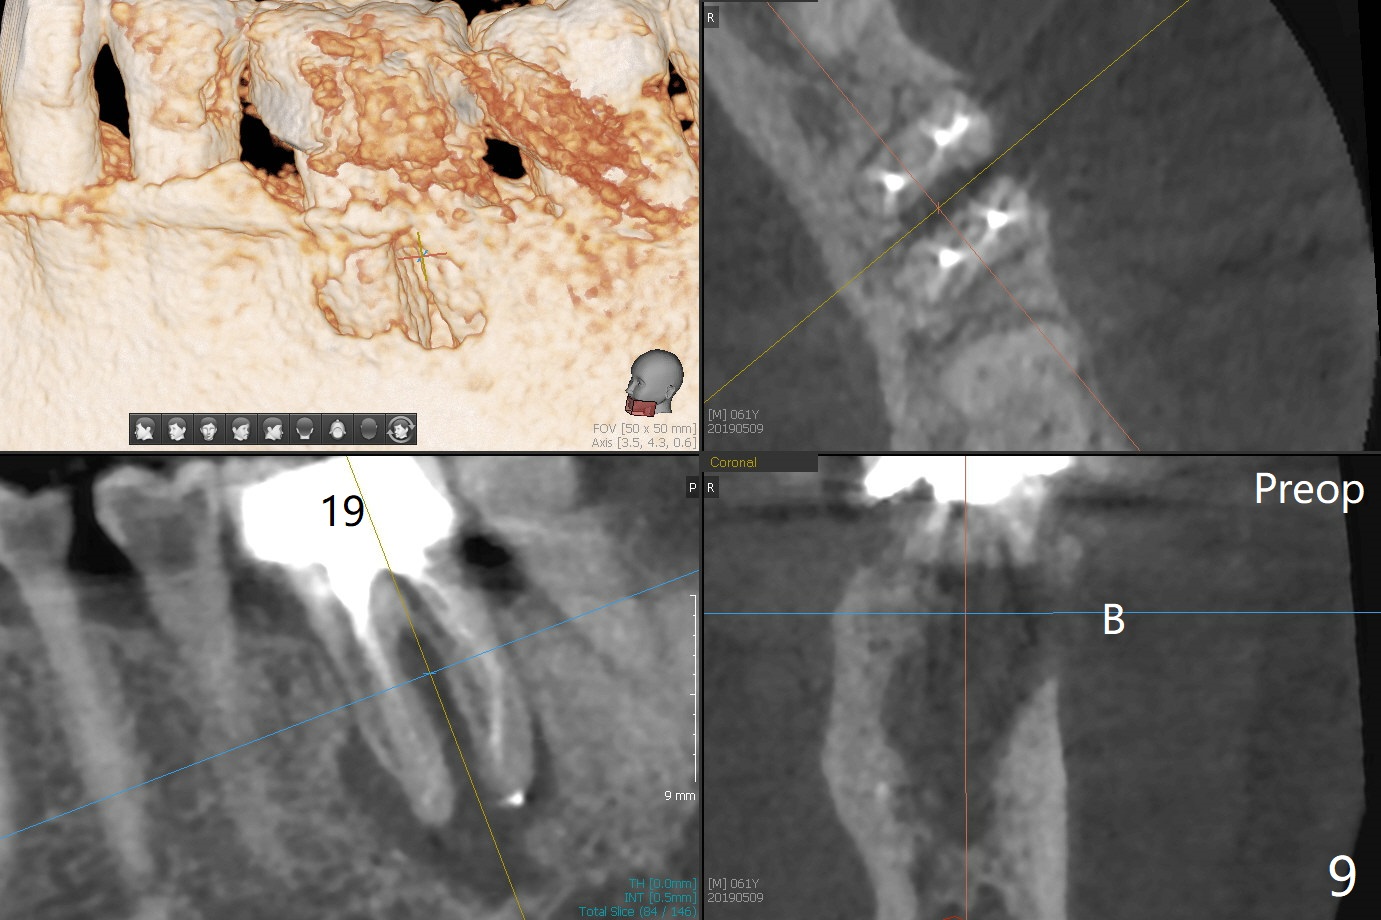

Bone Density Post Extraction with or without Bone Graft

Edentulous Lower Molar